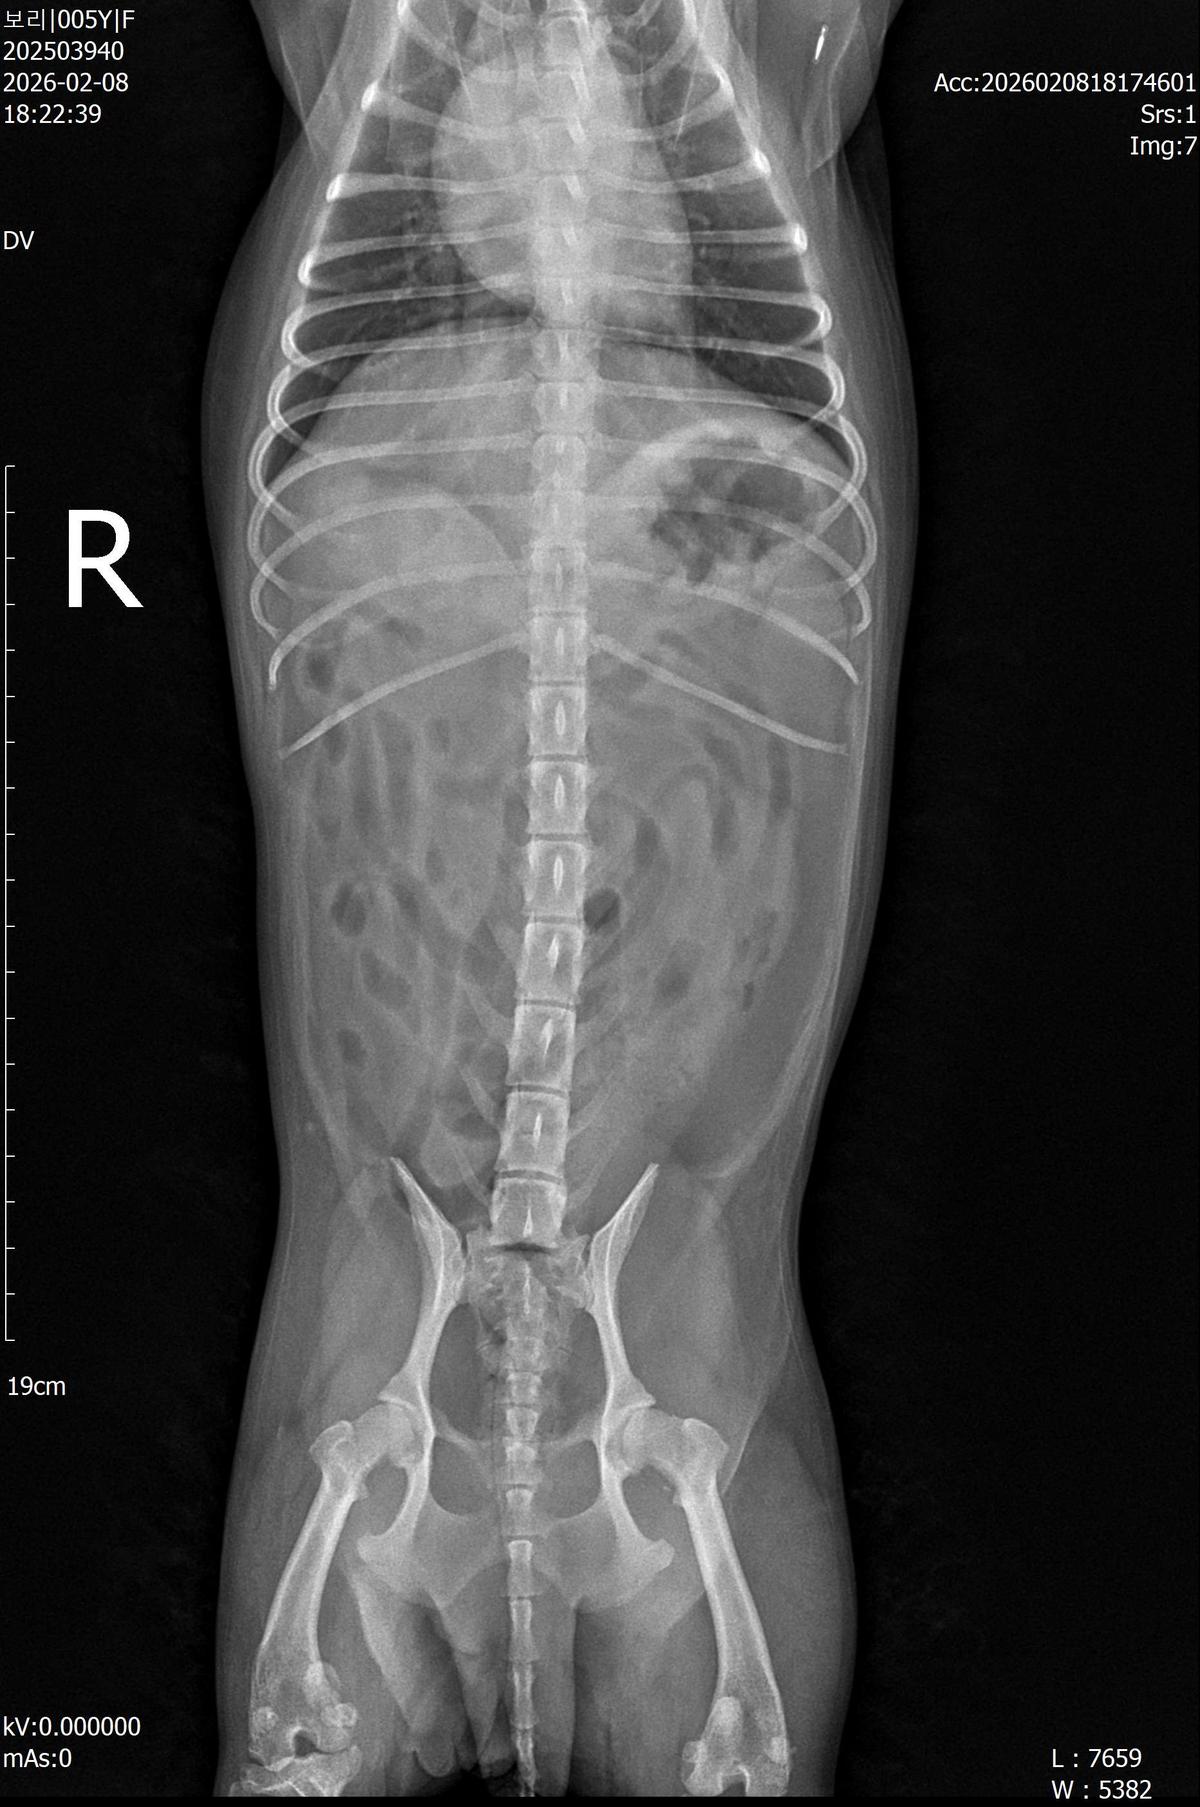

강아지 슬개골탈구 진단 받았습니다 몇군데 병원을 다녀봤는데 진단이 달라 궁금해서 질문 해봅니다 일단 저희 강아지는 오른쪽 다리를 갑자기 들고 다니고 절어 병원을 방문하게 되었고요 왼쪽은 증상이 없지만 오른쪽만 있는 상태였습니다 첫번째랑 두번째 병원에서는 슬개골 탈구 진행중이고 왼쪽이 3기 오른쪽이 2기 정도라고 했습니다 하지만 왼쪽은 아예 빠져있어 증상도 없고 아파하지도 않는다고 했고 오른쪽은 빠졌다 안빠졌다 해서 증상이 있다고 했고 십자인대가 파열된 걸론 보이지 않는다고 했습니다 그래서 양쪽 슬개골탈구 수술만 진행하면 된다고 했고요 근데 세번째 병원에서는 둘다 왼쪽이 좀 더 심한 슬개골 탈구 3기 정도라고 했고 오른쪽만 십자인대 부분파열이 보인다고 했습니다 그래서 십자인대 파열이 아닌 왼쪽은 굳이 수술할 필요가 없고 나중에 십자인대 파열이 오거나 증상이 나타나면 그때 수술하면 된다고 했습니다 그래서 오른쪽 슬개골탈구 수술과 tplo를 하는 방식으로 수술을 한다고 했습니다 여기서 궁금한점은 1. 십자인대 파열이 사진상으론 보이지 않는다고 하는데 사진상으로 알 수 있는 건가요? 2. 십자인대 파열이 아니면 슬개골탈구 수술을 굳이 할 필요 없다고 하셨는데 맞는 건가요? 3. 꼭 슬개골탈구와 십자인대 수술을 같이 해야 결과과 더 좋아지나요? 4. 사진상으로 십자인대와 슬개골 수술을 같이 해야할까요? 5. tplo 수술방법이 가장 안전하고 좋은 수술방법인가요? 6. 슬개골탈구로 인해 십자인대가 끊어지는건 아니라고 들었는데 맞나요? 슬개골 탈구 수술로 십자인대를 예방할 수 있나요?